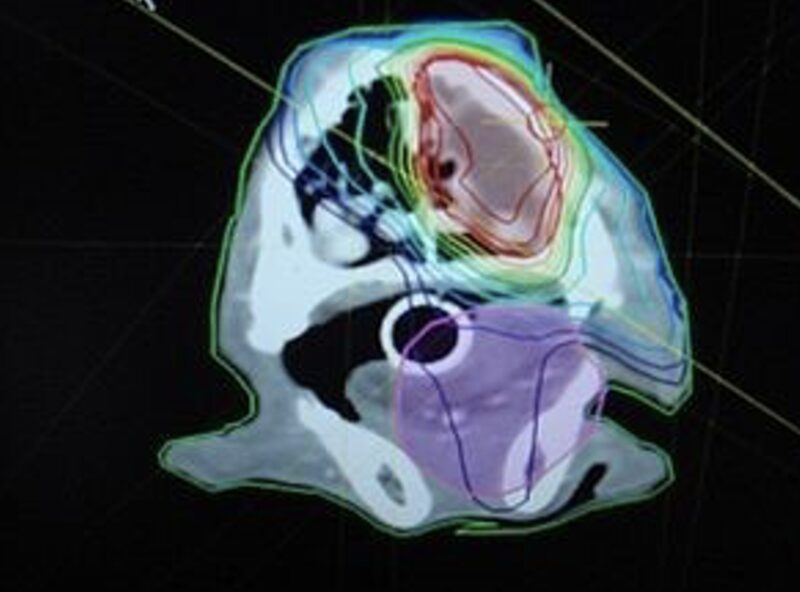

Durch IMRT kann die Strahlungsintensität so angepasst werden, dass sie der Form des Tumors folgt und gleichzeitig Risikoorgane wie Augen geschont werden (Abb. 4). Die Bestrahlung erfolgt aus verschiedenen Richtungen und mit variierenden Strahlungsstärken. Zusätzlich wird ein Multi- Leaf-Collimator (MLC, Abb. 5) eingesetzt, der aus zahlreichen röntgendichten Lamellen besteht. Diese Lamellen passen sich für jede Strahleneinheit an, so dass der Strahl optimal geformt wird, um der Anatomie des Tumors zu entsprechen. Dadurch wird das umliegende Gewebe bestmöglich geschützt.